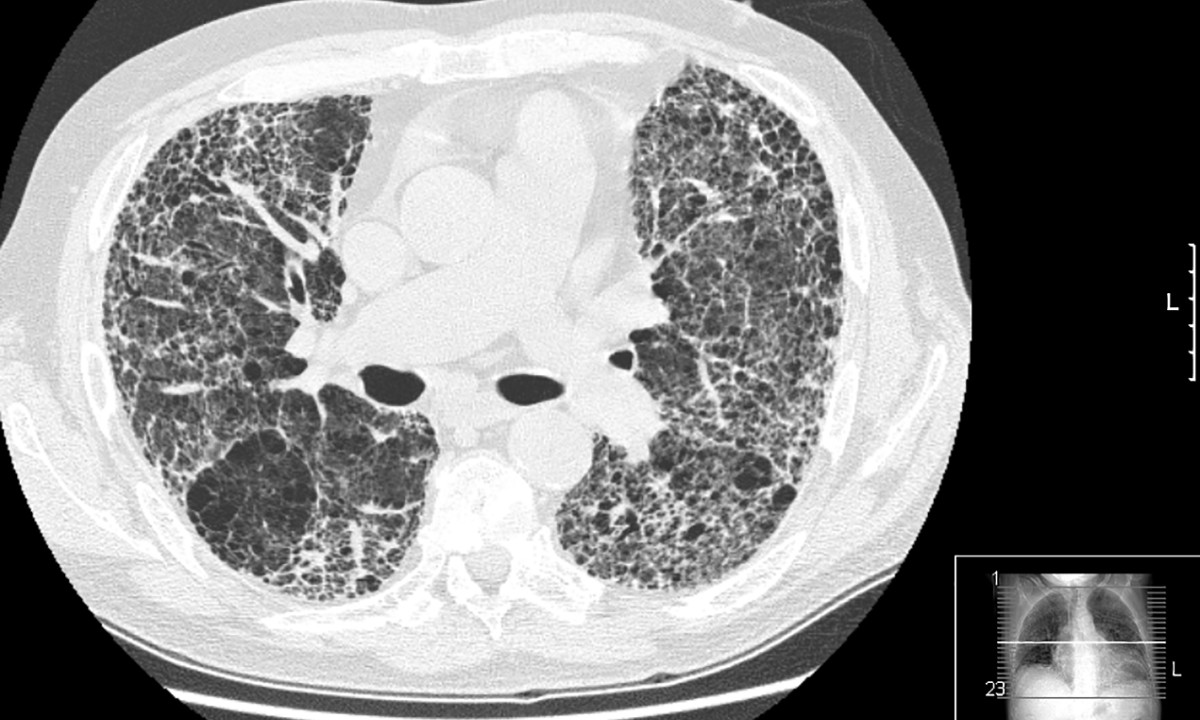

Idiopathic pulmonary fibrosis: promise on the horizon